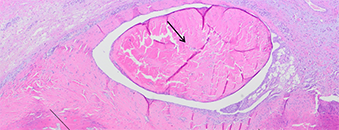

Fluctuerende bilaterale zwelling aan de plantaire zijde van de achterpoten, net proximaal van het grote zoolkussen. Uit de laesies werd beiderzijds 3-4 milliliter serohemorrhagisch vocht verwijderd.